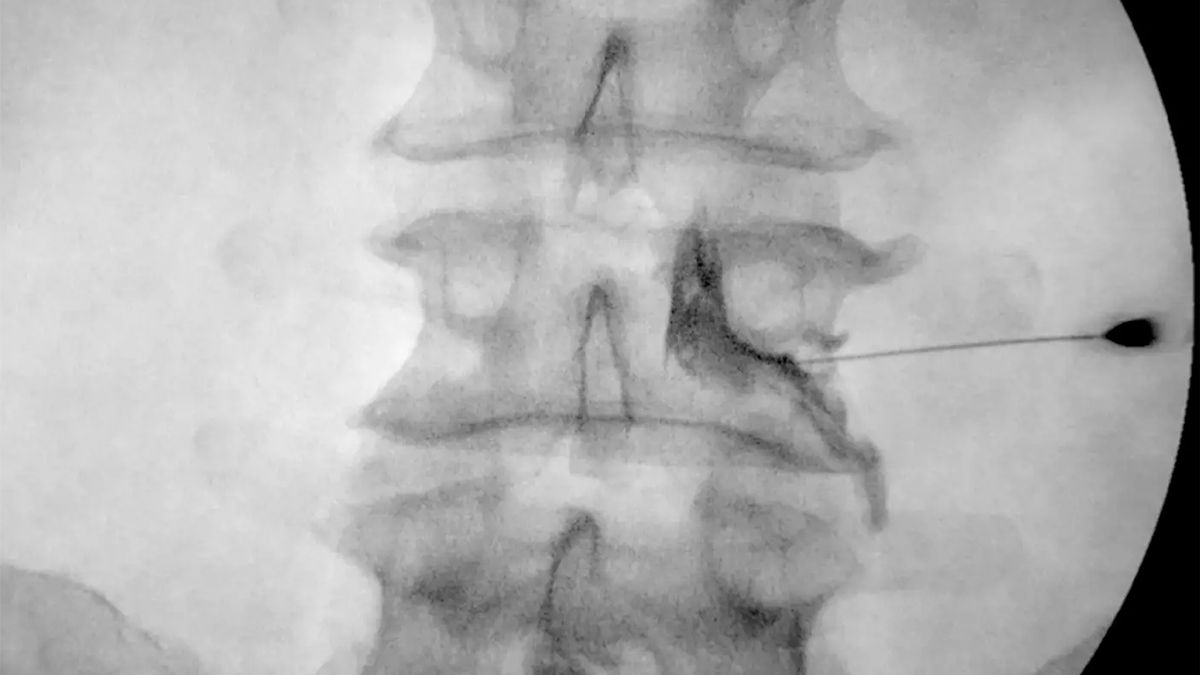

Y continúa: "El bloqueo radicular entonces consiste en llegar a través de la piel guiado por un equipo de radioscopía con una pequeña aguja hacia la raíz y administrar una medicación, que generalmente es una medicación antiflamatoria, para poder lograr desinflamar la raíz que esta en contacto con el disco".